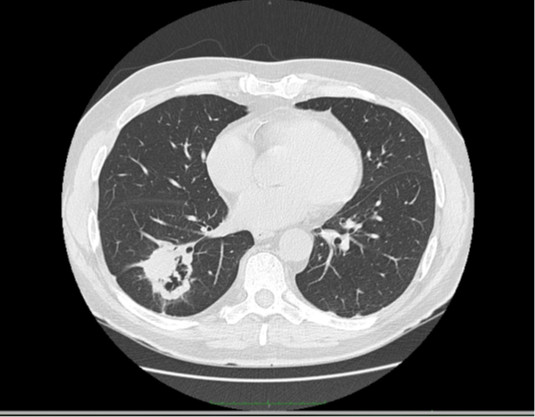

74-letni pacjent skierowany do poradni pneumonologicznej przez lekarza rodzinnego z rozpoznaniem nawracającego zapalenia płuc. Na podstawie wywiadu ustalono postępującą duszność wysiłkową, nikotynizm w wywiadzie 20-paczko lat. Choroby dodatkowe: nadciśnienie tętnicze dobrze kontrolowane. W ostatnim roku chory miał czterokrotnie podawane antybiotyki przez lekarza rodzinnego, lecz nigdy nie gorączkował. W badaniu fizykalnym stwierdzono obustronne metaliczne trzeszczenia nad dolnymi polami płucnym, w badaniach czynnościowych: FEV1/FVC 0,95; FEV1 35%N, FVC 28%N, TLC 32%N, DLCO 19,9 %N. Wykonano TK HRCT:

W oparciu o w/w: